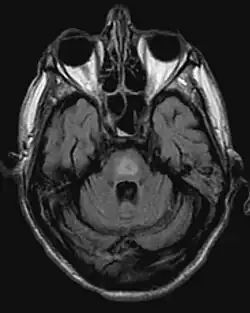

- Magnetresonanztomographie (Veränderungen oft erst nach einigen Wochen!)